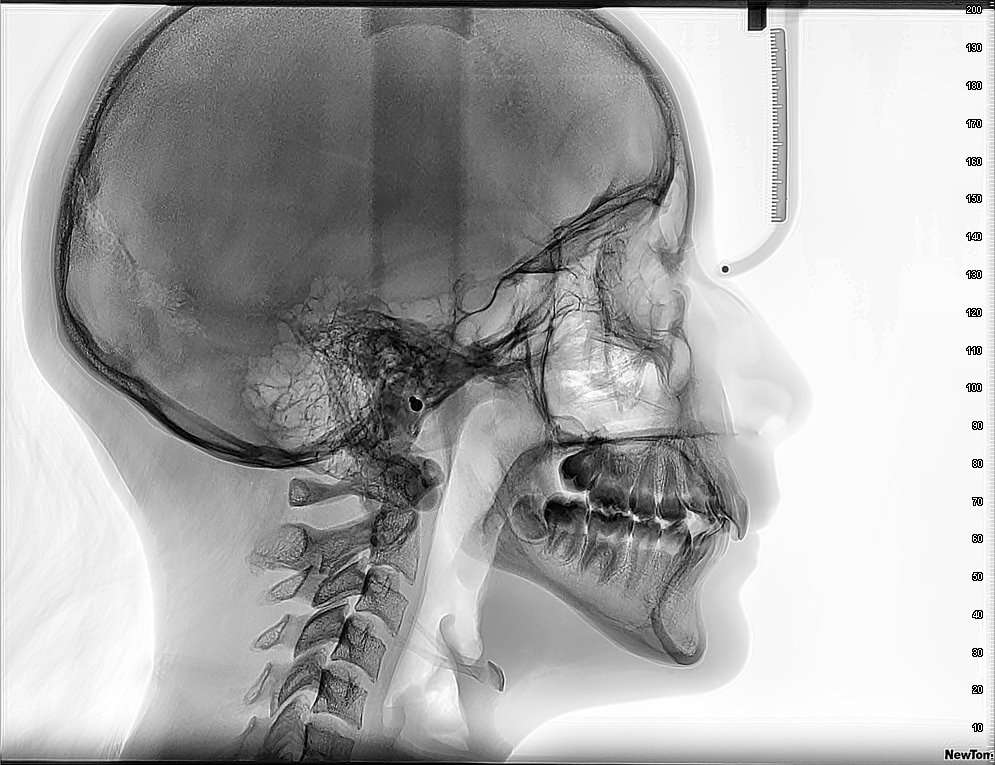

¿Por qué es crucial realizarse un examen de tac macizofacial regularmente?

Un examen de tomografía computarizada (TAC) macizofacial es una herramienta diagnóstica esencial en la medicina dental y maxilofacial. Este procedimiento …

Los beneficios del examen de tac macizofacial para el diagnóstico dental

El examen de TAC macizofacial, o tomografía axial computarizada macizofacial, es una técnica de imagen avanzada que permite obtener imágenes …